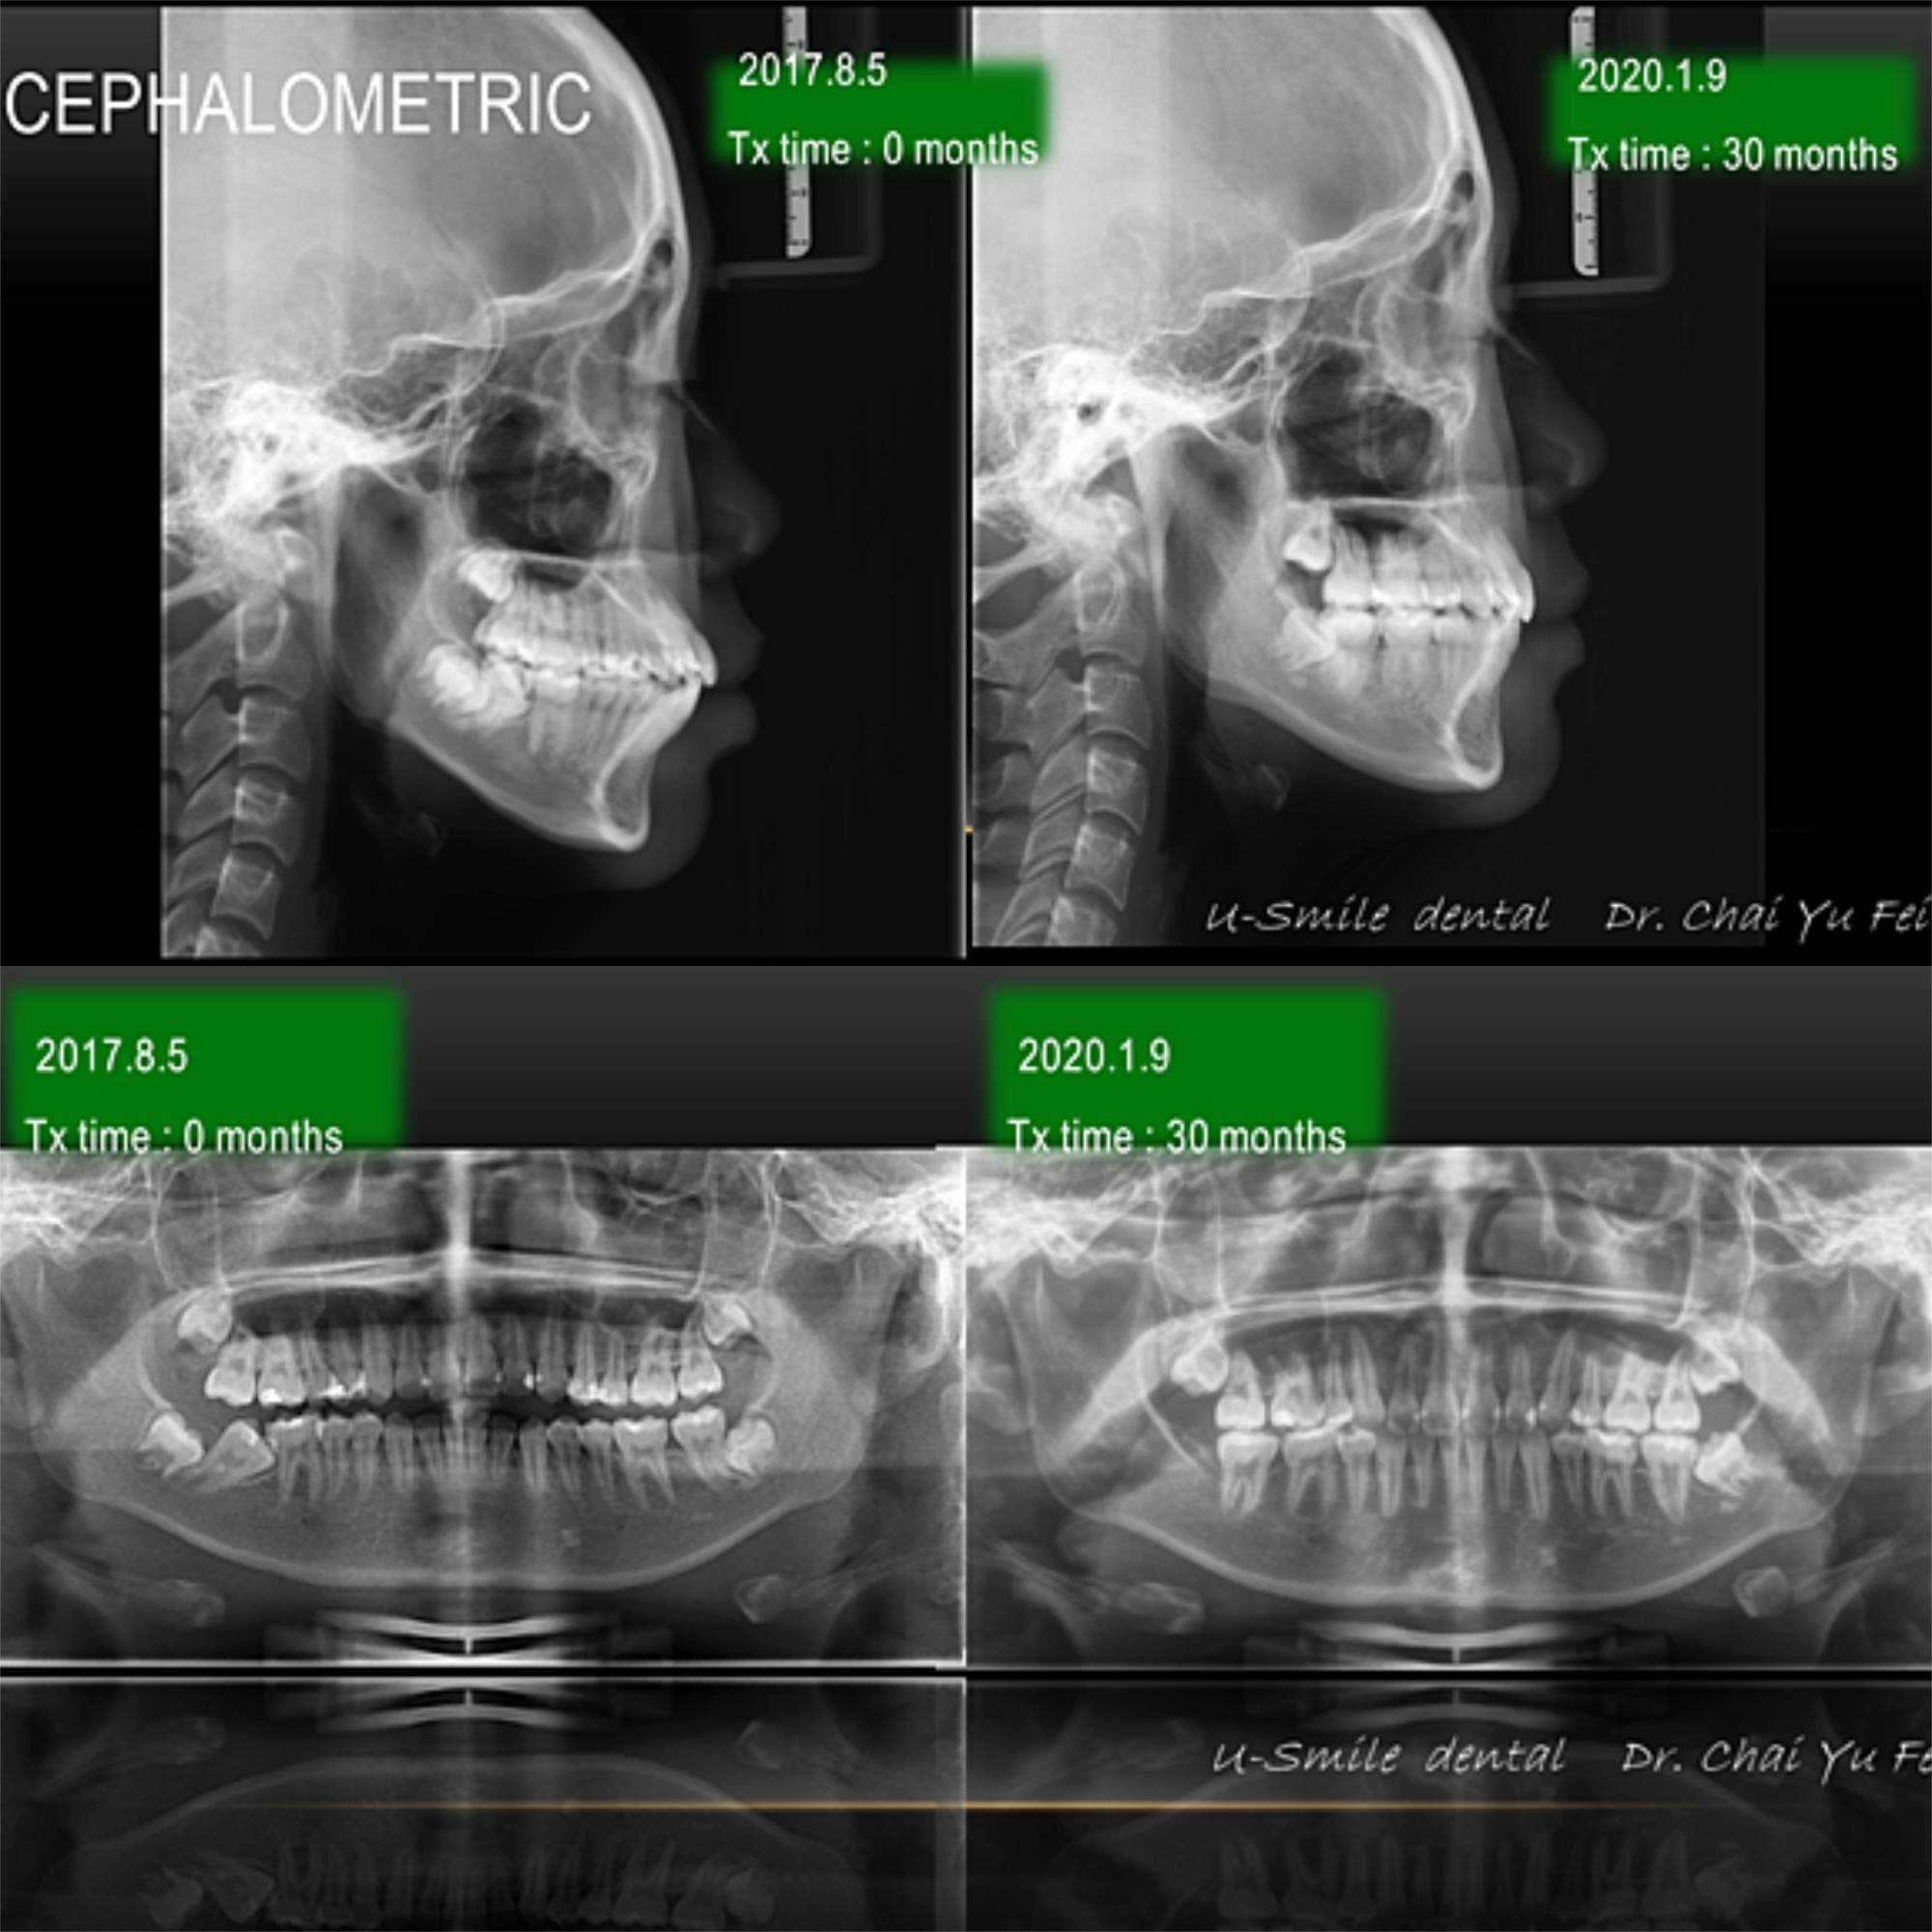

青少年臼齒扶正合併暴牙改善案例-A同學

[ 矯正醫師 ] : 展悅牙醫  翟聿飛 醫師

[ 治療方式 ] : 利用LH 線的超彈性將嚴重傾倒的第二大臼齒扶正。

[ 治療時間 ] : 30 個月

A同學來到診所,主要希望能夠解決右下傾斜的大臼齒,經過全面性的評估後,另外我認為她若拔掉小臼齒製造空間 ,前突的角度會改善非常多,

經討論之後,決定要合併拔牙治療解決前牙暴牙的狀況~

抜歯矯正治療によって、治療後では前歯の傾斜と前突が改善されたため、

上顎兩顆小臼齒的拔牙空間順利關閉。藉由骨釘後退達到理想咬合。下顎咬合平面整平後,再向內移動改善唇型。